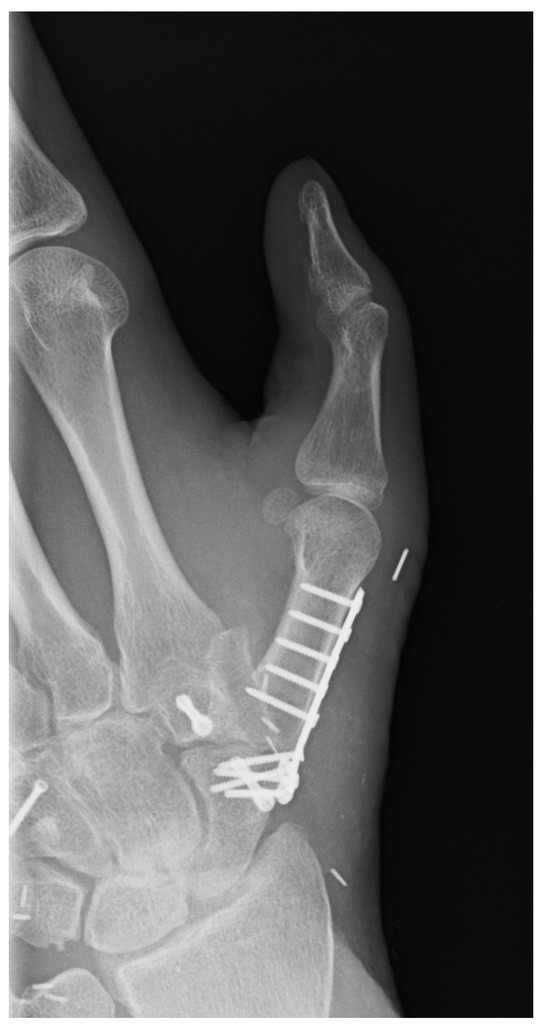

| 1 | 17 | m | Circular saw injury to the dominant left hand with a subtotal amputation of DII–DIV at the level of the MCP joints | Replantation of DIV Amputation of the distal metacarpals DII and DIII, PIP-Joint transfer to DII from the left second toe, MCP endoprosthesis DIII, Free double toe joint transfer to PIP and DIP from the right second toe | Finger-palm distance (FPD) DII–DV 0–0–1–0 cm Fingernail table distance (FNTD) DII–DV 0–0–0–0 cm Kapanji 10/10. DII: MCP 0–0–80°, PIP 0–0–100°, DIP 0–0–80°; DIII: MCP 0–0–80°, PIP 0–0–100°, DIP 0–0–50°; DIV: MCP 0–10–90°, PIP 0–0–90°, DIP 0–0–10°; DV: MCP 0–0–90°, PIP 0–0–100°, DIP 0–0–90°. | The two-point discrimination reached 4–6 mm in all fingers. | Pinch left 7 kg, right 10 kg. Force left 8 kg, right 18 kg. |